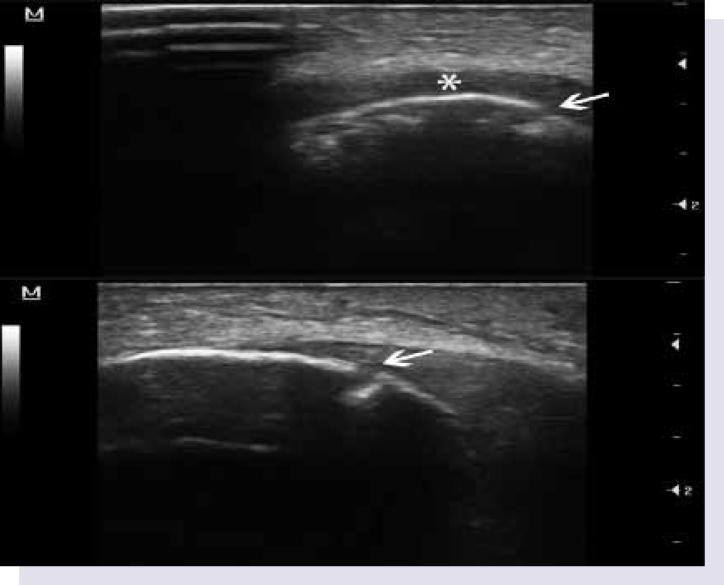

Ultrasonographic Examination of Patella.

https://cdn.ncbi.nlm.nih.gov/pmc/blobs/df14/4909935/f275626f7b7f/gr1.jpg